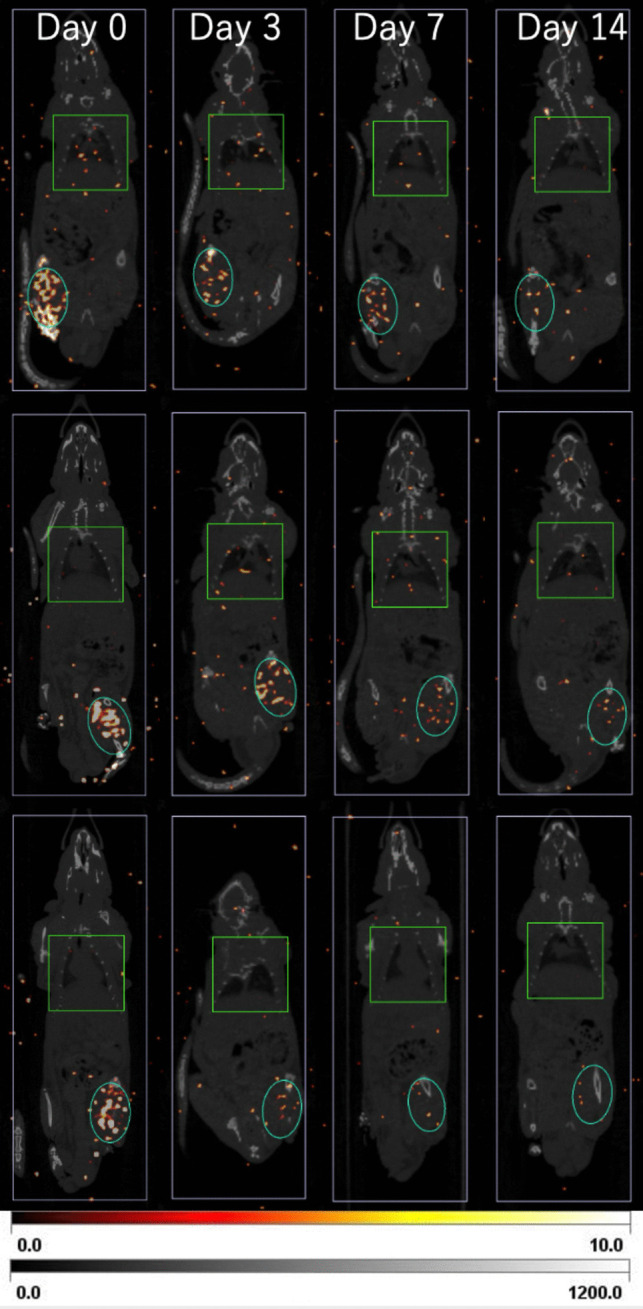

Methods: After synthesizing 177Lu-oxine from 177Lu-chloride, the product was emulsified in lipiodol. Its radiochemical purity and partition coefficient were measured. F344 NJcl rnu/nu rats (n = 5) bearing bilateral thigh tumors (HC-4 cells) were randomized to receive 177Lu-lipiodol (2.8 MBq in 50 μL) or non-labeled lipiodol (50 μL) via surgical exposure and direct puncture of the right femoral artery. SPECT/CT images were acquired over 14 days, and biodistribution was confirmed by gamma counting at day 28. Tumor volumes and body weights were monitored to assess treatment response and toxicity.

Results: The 177Lu-lipiodol emulsion was obtained with a high radiochemical purity (> 99%). SPECT/CT showed high tumor accumulation (34.0% ± 4.4% immediately post-injection) that persisted up to day 28 (7.3% ± 1.2% of injected dose). Tumor growth was significantly suppressed with a treated-to-untreated volume ratio of 0.45 at day 14 (p = 0.017) and 0.59 at day 21 (p = 0.001). While off-target uptake was limited, moderate splenic accumulation (26.6% ± 17.5% ID) was noted. No marked body weight changes or gross organ abnormalities were observed.